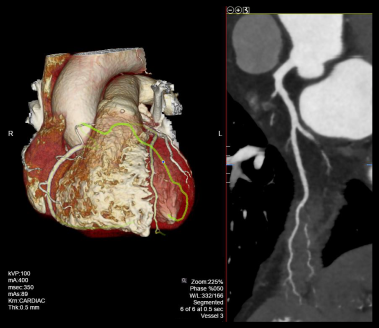

- Curved planner reformations (CPRs) of coronary arteries.

- 3D reconstructed and maximum intensity projection images.